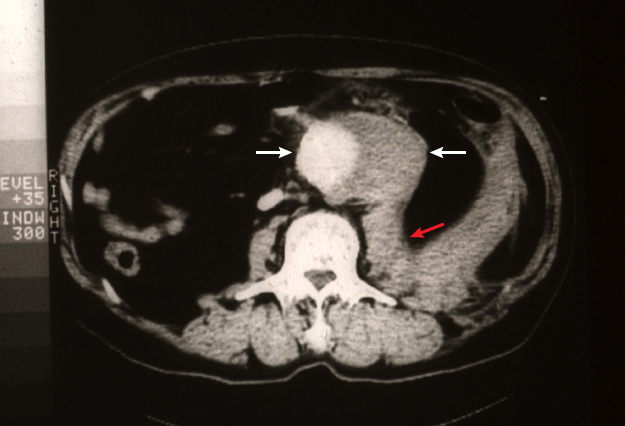

大動脈瘤は、大きくなっても無症状で経過することが多く、患者さんが自覚することはほとんどありません。通常は、X線撮影やCT検査などで偶然発見されることが多いです〈図1 a,b,c〉。

直径3cm以上は腹部大動脈瘤と定義され、腎動脈下腹部大動脈に好発します〈図1 a,b,c〉。動脈瘤は年間に約0.5cmずつ拡大していきます。瘤径が4cmを超えると、1年以内に破裂する危険性が約15%に達するため、一般的に4〜5cmを手術の適応としています。〈図2〉。

図1

図1. 腹部大動脈瘤

• 腹部大動脈〜腸骨動脈瘤の模式図

• 腹部大動脈瘤(矢印)の大動脈造影像

• 腹部大動脈瘤(矢印間)の CT 画像